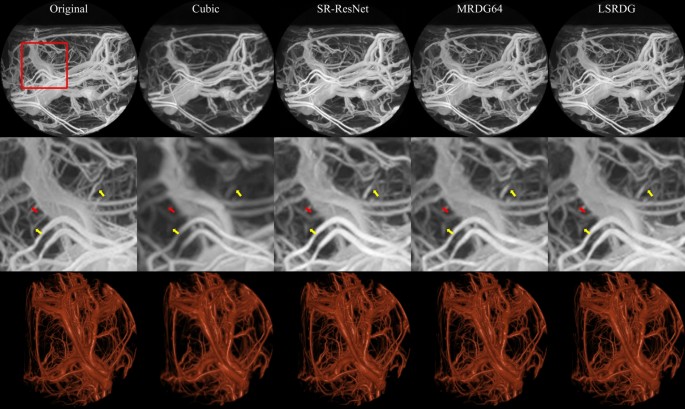

The performances of the networks trained with and without GAN were compared using SSIM, PSNR, and MSE as shown in Tables 2 and 3. Our proposed model trained both with and without GAN significantly outperforms the other models in all evaluation metrics and reconstructs an image that is similar to the original HR image. Figures 3 and 4 show a visual comparison of SR images and residual maps respectively generated using PSNR-only oriented models on HC data. In addition, Fig. 5 shows the visual comparison of generated SR images using a combination of PSNR and GAN-oriented models on HC data. As indicated by the arrows in Figs. 3 and 5, the bifurcation of blood vessels was visualized better using our proposed model compared to others in both modes of training.

Visual comparison of generated images using PSNR-oriented training on HC data. The first row shows images after maximum intensity projection in the coronal direction. The second row shows the focused region (marked by the red square in the top row), and the third row shows the volume-rendered data. The yellow and red arrows on the images show the bifurcation points of the blood vessels that are successfully reconstructed by our model only (yellow arrows) and not reconstructed by any model (red arrows).